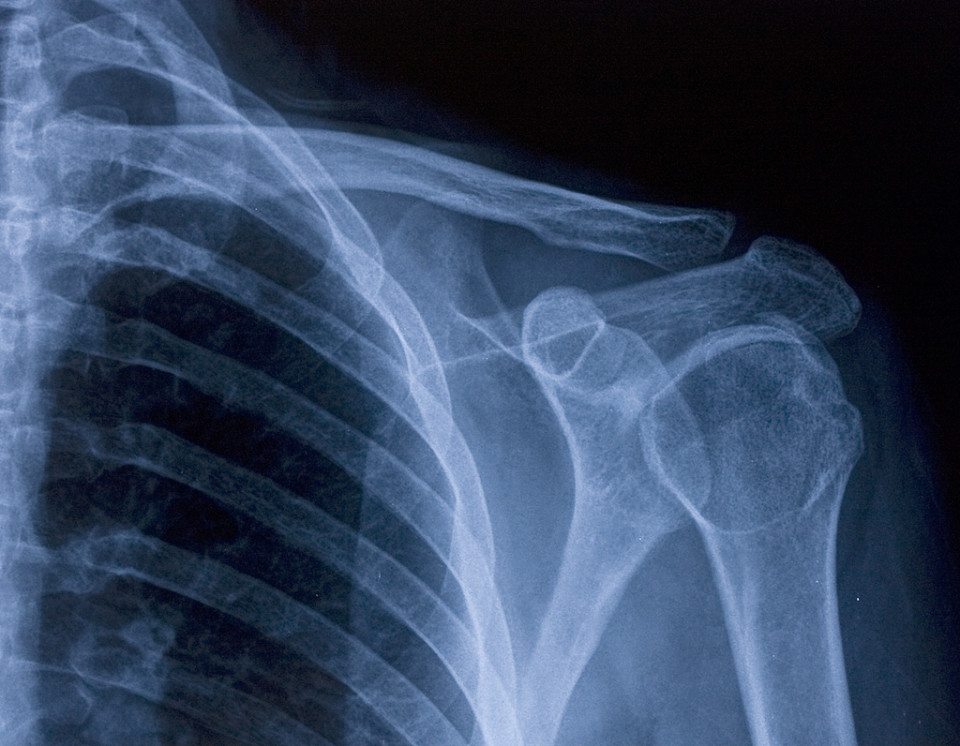

dr肩关节正位片

图片尺寸1280x1706